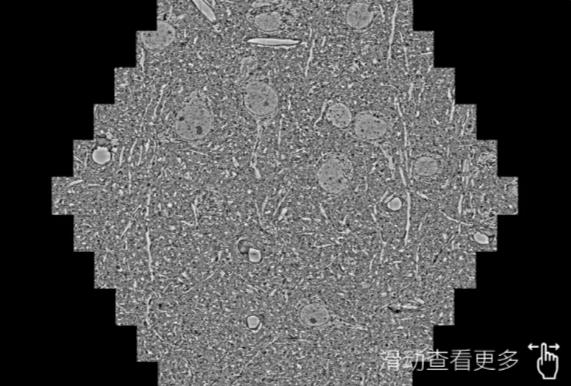

鼠脑切片。左图使用大庆蔡司大庆扫描电镜MultiSEM706对165μmx143pm面积区域成像,耗时仅需1.5秒。右图为鼠脑切片中30μm区域放大效果。样品由芝加哥大学B.Kasthuri提供。

使用蔡司高速大庆扫描电镜MultiSEM对1mm²人脑皮层组织进行高分辨成像,并对其中的各种细胞结构进行三维重构分析。左图展示了2x3mm²组织平面中锥体神经元的三维重构效果。右图显示了局部体积神经元三维重构。图像由哈佛大学chtman实验室提供,渲染图由D. Berger 制作。